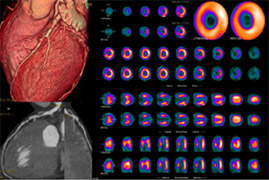

Cardiac Pet/ct

Enhance your business with our stunning commercial Cardiac Pet/ct collection of numerous professional images. optimized for commercial use with truck, vehicle, and automobile. ideal for corporate communications and branding. Discover high-resolution Cardiac Pet/ct images optimized for various applications. Suitable for various applications including web design, social media, personal projects, and digital content creation All Cardiac Pet/ct images are available in high resolution with professional-grade quality, optimized for both digital and print applications, and include comprehensive metadata for easy organization and usage. Discover the perfect Cardiac Pet/ct images to enhance your visual communication needs. Our Cardiac Pet/ct database continuously expands with fresh, relevant content from skilled photographers. Reliable customer support ensures smooth experience throughout the Cardiac Pet/ct selection process. Professional licensing options accommodate both commercial and educational usage requirements. Multiple resolution options ensure optimal performance across different platforms and applications. Regular updates keep the Cardiac Pet/ct collection current with contemporary trends and styles. Each image in our Cardiac Pet/ct gallery undergoes rigorous quality assessment before inclusion. Time-saving browsing features help users locate ideal Cardiac Pet/ct images quickly. The Cardiac Pet/ct archive serves professionals, educators, and creatives across diverse industries. Comprehensive tagging systems facilitate quick discovery of relevant Cardiac Pet/ct content.